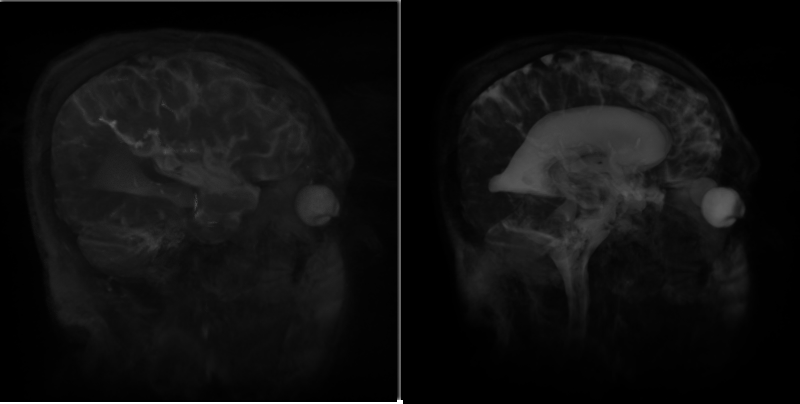

Figure 41.2 shows a basic image of ventricles of the brain on the left and an image of ventricles of the brain using BoundaryEnhancementVolumeStyle on the right.

Figure 41.2 — On the left, the ventricle with default render style and default field values. On the right, the ventricle using BoundaryEnhancementVolumeStyle with default values: boundaryOpacity=0.9, opacityFactor=2, and retainedOpacity=0.2.